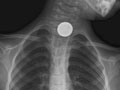

- Find foreign objects, such as coins or

other small pieces of metal, in the tube to the stomach (esophagus), the

airway, or the lungs. A chest X-ray may not be able to see food, nuts, or wood

fibers. .

seen. | A foreign object is seen in

the esophagus, breathing tubes, or lungs. | A tube, catheter, or other